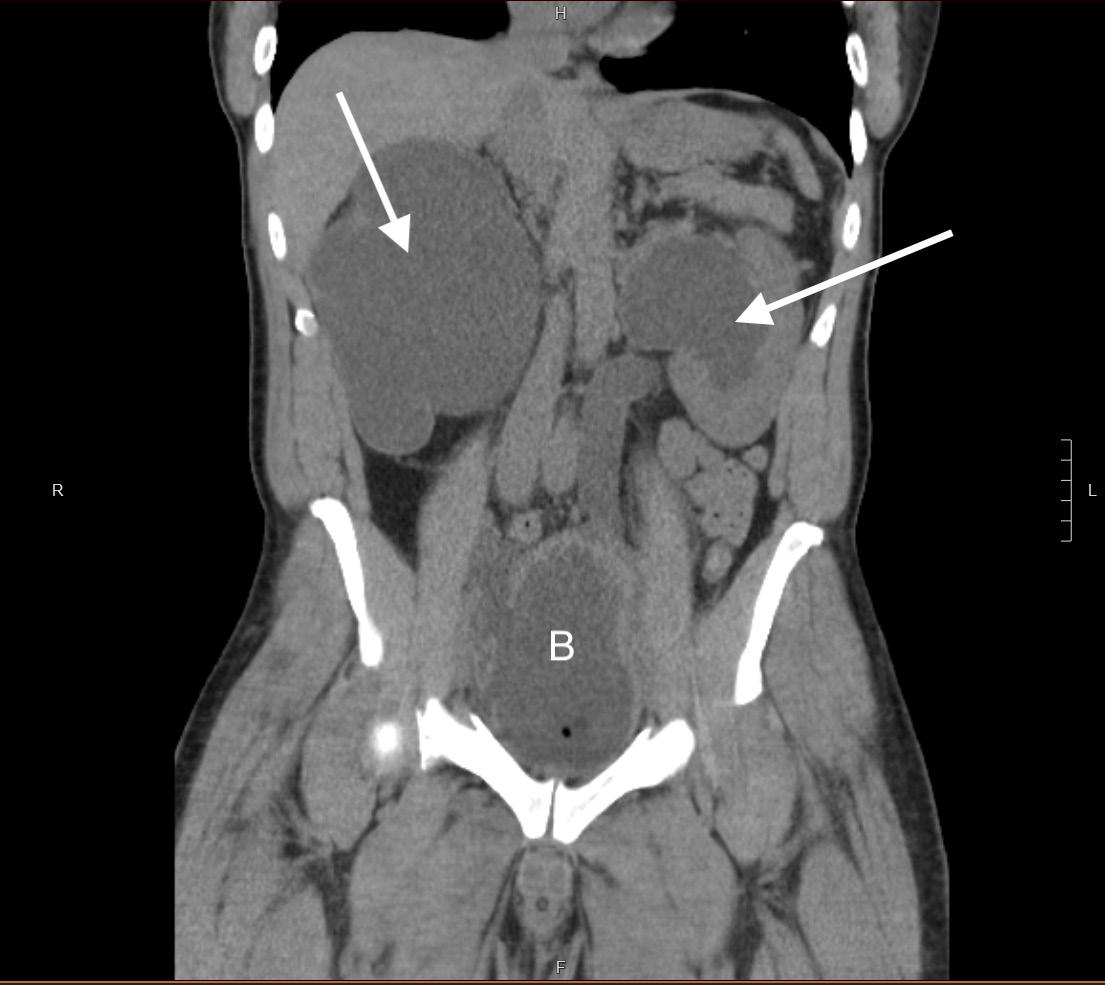

calculate bicarbonate and base excess due to a pH more than 7.70. The patient underwent an abdominal ultrasound in the ED, which suggested IHPS with an enlarged pyloric channel measuring 2.1 cm and a thickened muscle measuring 0.5 cm, again with minimal passage of fluids through the pylorus (Image 1). The surgical team was consulted for the abnormal laboratory and ultrasound findings, but due to the possibility of postoperative edema or residual abnormal external pylorus measurements, the consultant recommended further imaging to conclusively determine pyloric stenosis. The child was admitted for fluid resuscitation and electrolyte replacement. An upper GI series performed the same day confirmed the diagnosis of IHPS when there was lack of contrast passing from the stomach to the duodenum. The patient received a solution of intravenous 5%, dextrose, half normal saline, and 40 mEq potassium chloride at maintenance until electrolytes and intravascular volume

Case Report: An eight-week-old boy with a history of IHPS about six weeks status post pyloromyotomy presented to the ED with vomiting and failure to thrive, and a critically narrowed pylorus was identified by ultrasound. An upper gastrointestinal series confirmed recurrent pyloric stenosis, necessitating another pyloromyotomy.